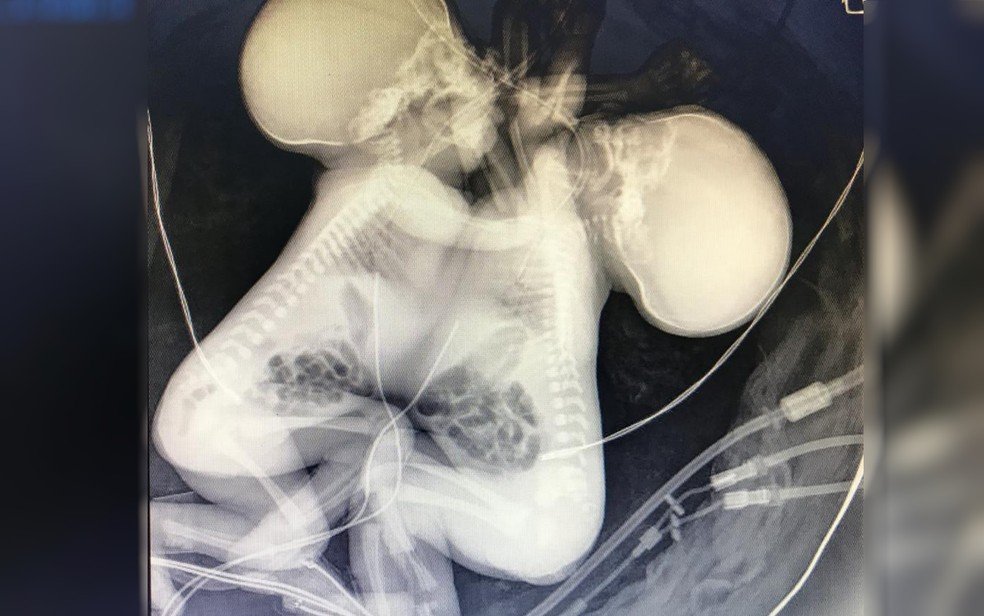

A gêmeas siamesas, que nasceram unidas pelo tórax e compartilhando o coração, morreram na tarde desta quarta-feira (02), em Goiânia. A informação foi confirmada pelo Hospital Estadual Materno Infantil Jurandir Nascimento (HMI). A mãe delas veio da Bahia para o parto na capital goiana.

Segundo a nota divulgada pelo hospital, as meninas estavam internadas na Unidade de Terapia Intensiva Neonatal (UTIN), e a causa da morte foi devido à má formação cardíaca.

As gêmeas nasceram na quinta-feira passada (26) com 34 semanas de gestação. Juntas, as irmãs pesaram 3.044 kg. Ainda de acordo com o HMI, o velório vai acontecer na cidade dos familiares, que fica na Bahia, e a família não quer falar sobre o assunto.

Segundo ele, uma tinha o coração com tamanho normal, e outra com coração menor. Por conta disso, segundo o médico, uma mantinha a outra por meio de uma veia que comunicava os dois corações.

A cirurgia de separação das meninas era impossível, de acordo com Calil, já que os corações eram juntos, colados, músculo com músculo.